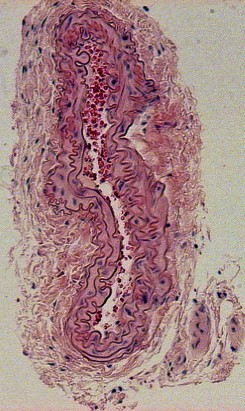

H&E (Haemotoxylin and Eosin) Staining

Ligation of Right External Carotid Artery Day-3 Post Procedure

Day-7 Post Procedure Day-14 Post Procedure Day-21 Post Procedure